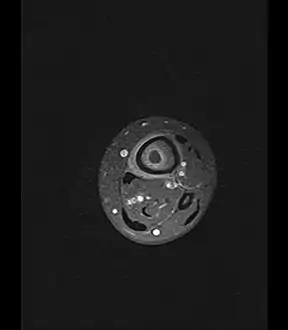

Axial T1-weighted MRI pre-contrast enhancement showing that the intramedullary collection is T1-hyperintense suggesting proteinaceous viscous fluid consistent with infection.